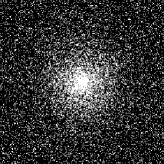

4.1 Phantom experiments

For the piecewise constant phantom experiments, we first compute the fully sampled k-space data using Eq. 3.1 with a piecewise constant function model Eq. 3.6. More precisely, given that ΩjsubscriptΩ𝑗\Omega_{j}’s are ellipses, Eq. 3.6 can be explicitly written as

where J1subscript𝐽1J_{1} is the first kind Bessel’s function of order 111. Then using the variable density random sampling method in [46], we generate 20%percent2020\% undersampled k-space data. The complex white Gaussian noise is also added so that the resulting SNR of the samples is approximately 25dB25dB25\mathrm{dB} (See Fig. 3).

Refer to caption

(a) Fully sampled

(b) Ground truth

(c) Sample mask

(d) Undersampled

Figure 3: Dataset for the phantom experiments. Fully sampled k-space data, its inverse DFT as a ground truth, the undersampling mask, and the undersampled k-space data.